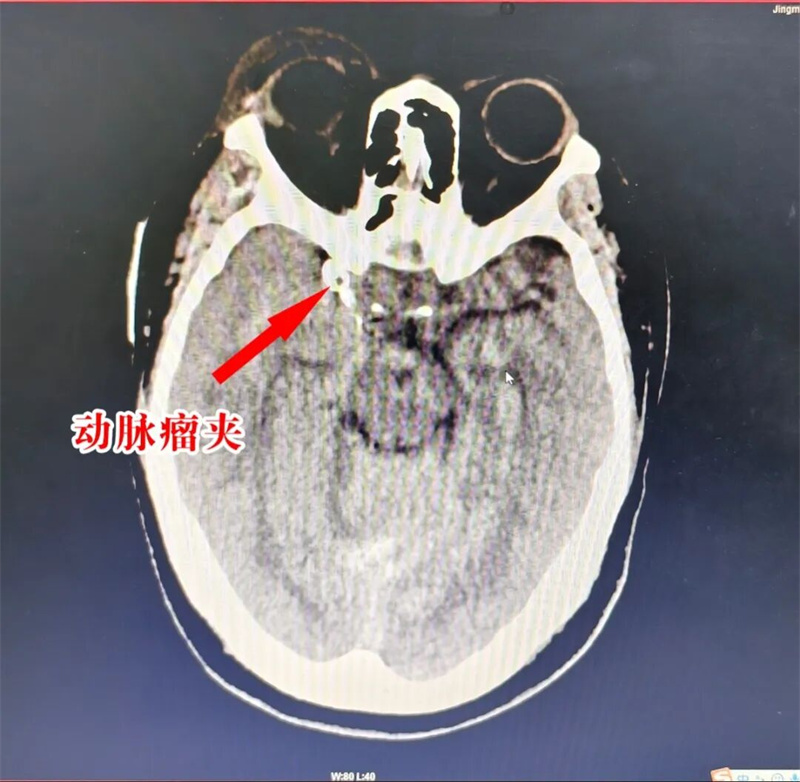

术后CTA显示:破裂的动脉瘤成功夹闭

迅速阻断右侧颈内动脉后,随着“咔嗒”两声,两枚动脉瘤夹果断夹闭瘤颈及部分瘤体,随即造影显示动脉瘤夹闭完全,载瘤动脉及重要穿支血管血流通畅,没有出现缺血迹象。